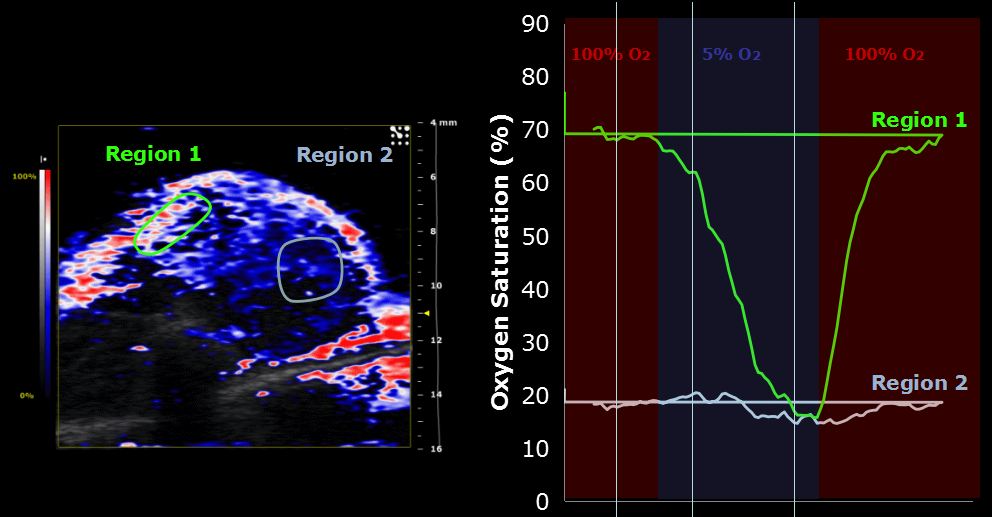

活体成像作为一种技术手段在生物医学特别是转化医学中具有重要的功能并得到越来越广泛的应用。Vevo® 2100 是VisualSonics公司的产品,Vevo® 2100 成像系统是第一个带有线性阵列技术和彩色多普勒功能的高频率、高分辨率数字成像平台。Vevo® 2100 成像系统集多项技术突破于一身,其中最突出的是用于小动物成像技术的高频线性阵列技术的开发。

肿瘤成像

分子成像